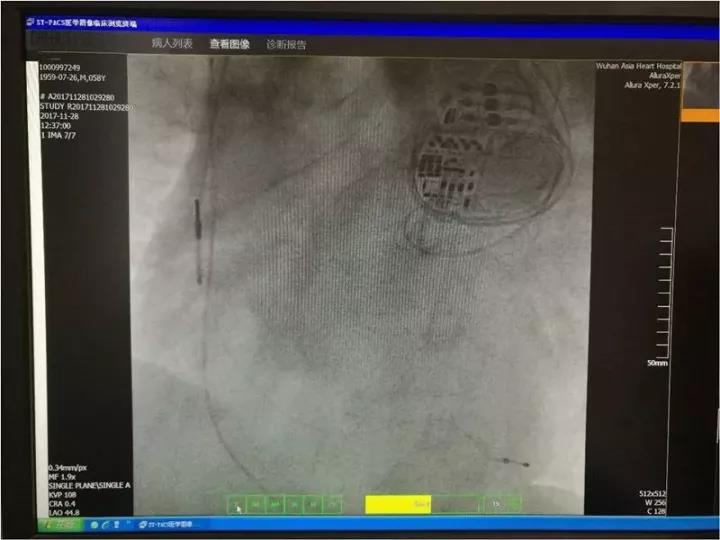

2017年11月28日,武汉亚洲心脏病医院李振主任,为该患者实施带有AdaptivCRT功能的CRT(C5TR01)。

QRS从术前176ms缩短至102ms。